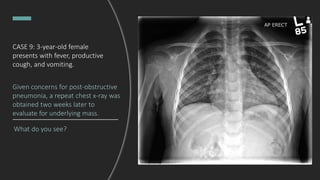

CASE 9: 3-year-old female

presents with fever, productive

cough, and vomiting.

Interpret this chest X-ray.

Right upper lobe pneumonia with

tracheal deviation towards the area of

consolidation. Per the radiology read,

ddx includes bacterial pneumonia or

post-obstructive pneumonia.

Given concerns for post-obstructive

pneumonia, a repeat chest x-ray was

obtained two weeks later to

evaluate for underlying mass.

What do you see?

Final Dx: Bacterial pneumonia

Normal chest x-ray!